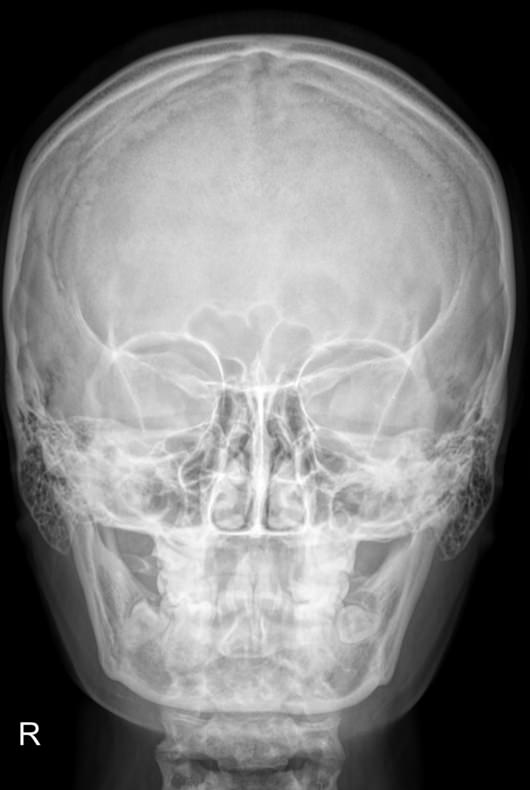

Череп устроен крайне сложно, так как содержит в себе множество важнейших органов: головной мозг и его кору, черепно-мозговые нервы, железы внутренней секреции, органы зрения, слуха и частично ― дыхательной и пищеварительной систем. Для каждого есть свой специфический участок с уникальным строением. Несмотря на то, что большинство этих органов относительно мягкие, они оказывают свое влияние на твердые кости черепа, оставляя на них следы при патологических изменениях. Поэтому рентген, как наиболее доступный и эффективный метод диагностики костной ткани, назначается одним из первых.

Снимки черепа требуют специального подхода во время рентгенодиагностики. Одно из основных требований ― соблюдение симметричности правой и левой стороны при фронтальной, то есть прямой рентгенографии. Также часто назначают снимок в боковой проекции, реже ― подбородочную, затылочную и прицельные снимки определенных костей.

В протоколе рентгенолог описывает следующие элементы:

• Кости, их форма, размеры, соотношение, видимость швов;

• Толщина костей в разных участках;

• Контуры внешние и внутренние;

• Следы «пальцевых вдавлений» и сосудистый рисунок;

• Состояние турецкого седла, его числовые значения;

• Наличие воздуха пазухах и их состояние;

• Переломы;

• Участки обызвествления;

• Новообразования.